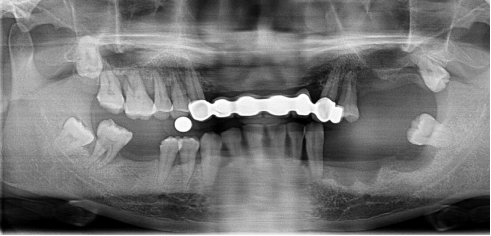

半口牙種植修復(fù)案例

病例簡(jiǎn)介:周女士,女,57歲,家住泉州,因下半口牙在當(dāng)?shù)胤N植不成功而來我院就診。

劉斌元教授在為該患者做了詳細(xì)的檢查后表示:“周女士由于先前種植牙的失敗,造成對(duì)口腔牙槽的破壞比較嚴(yán)重,需要重新做手術(shù)修整牙槽”

決定種植方案后,劉斌元教授分別為周女士做了三次診療,第一次做電腦種植前準(zhǔn)備;第二次做電腦種植手術(shù),覆蓋義齒恢復(fù);第三次做固定義齒修復(fù)。目前周女士的半口牙齒已種植完畢,果很好。